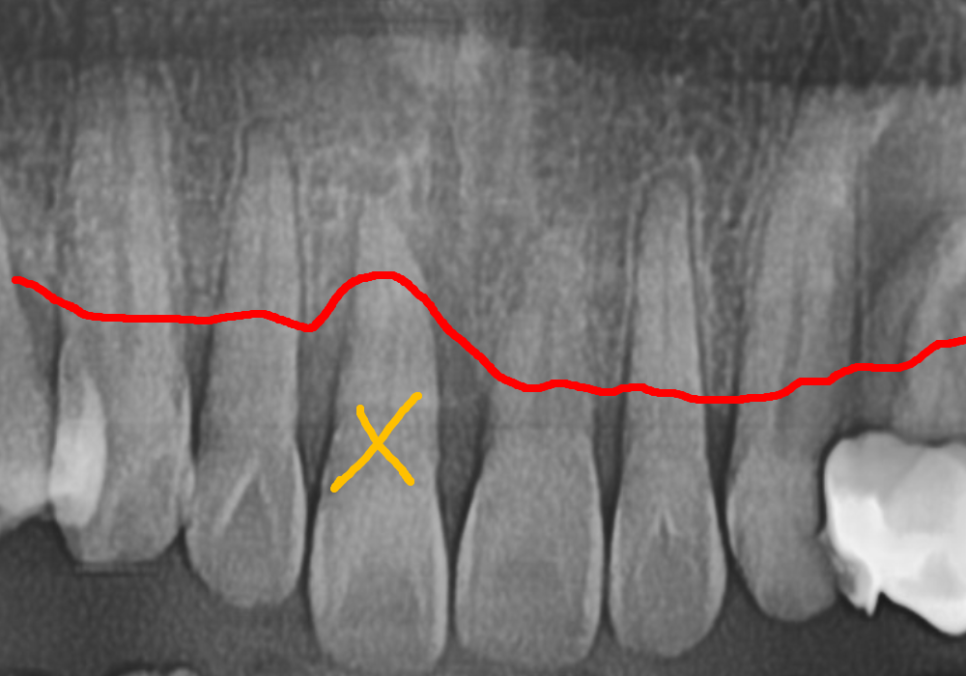

방사선 사진을 살펴보니,

옆 치아들에 비해 잇몸뼈가 많이

낮아진 걸 확인할 수 있었습니다.